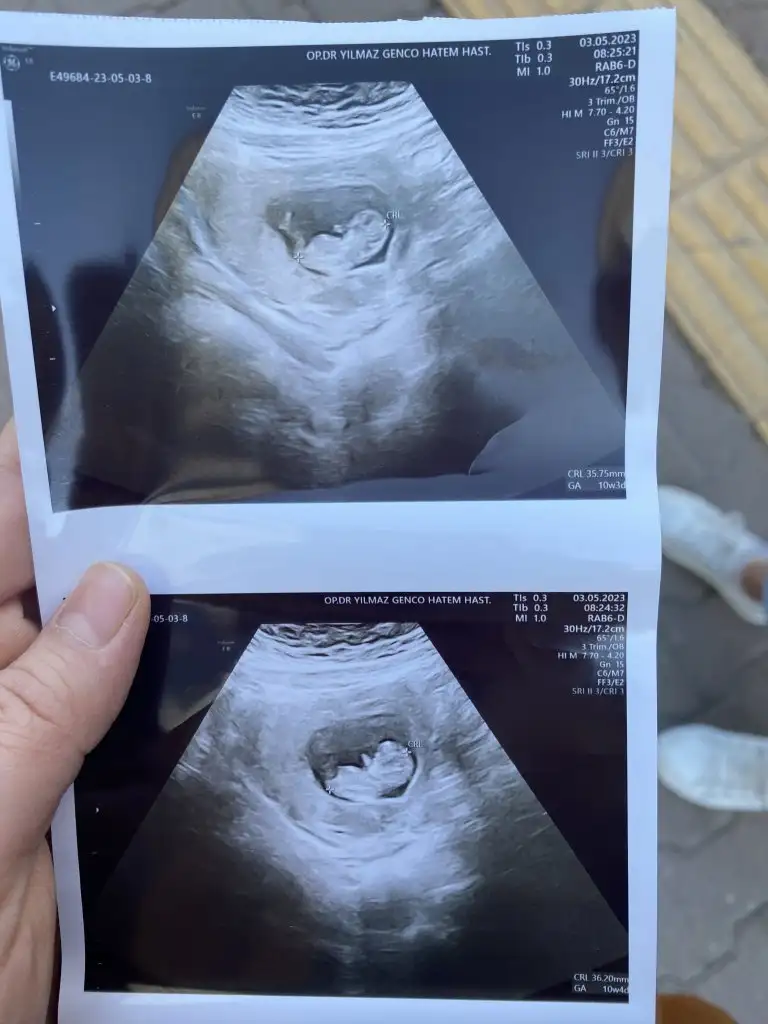

6-7 haftalık Ramzi teorisine 10-11-12 de nub teorisine göre tahmin yapıyoruZ🤭

banada tahminde bulunurmusunuz